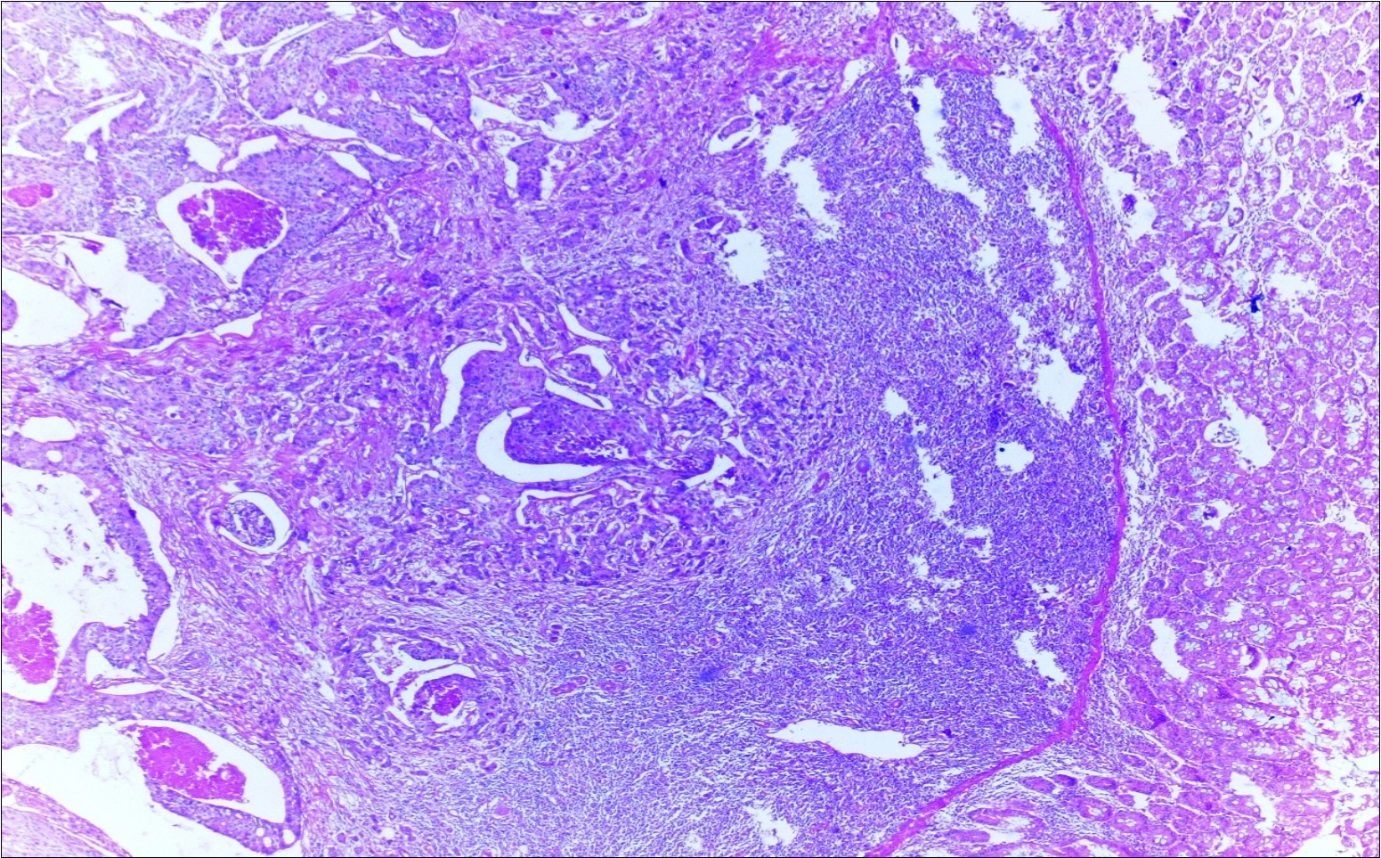

A 63-year-old woman presented to the Department of General Surgery as an outpatient with abdominal pain. Physical examination showed the signs of acute appendicitis and appendectomy was performed. During microscopic examination, a small focus of atypical monotonous lymphoid cell population was seen and the material was sampled totally. The pathological examination revealed MALT lymphoma (Figure 1), with diffuse positivity of cluster of differentiation (CD) 20 (Figure 2), CD 79a and B-cell lymphoma (Bcl- 2) (Figure 3) with just a few CD3 positive lymphoid cells. However, no evidence of adenocarcinoma was found in the appendectomy specimen. After the diagnosis of lymphoma, a complete colonoscopy was planned and this revealed a solid tumoral mass in the caecum measuring 5x4x4 cm. Computed tomography of the abdomen and pelvis revealed mesenteric lymphadenopathy associated with a mass in the caecum with multiple nodules in liver consistent with metastasis (Figure 4). Frozen sections were not obtained since the treatment method would not be affected. The patient underwent anterior resection with regional lymphadenectomy, with the pathological assessment of the resected specimen revealing a collision tumor consisting of a poorly differentiated adenocarcinoma extending through the muscularis propria with MALT lymphoma (Figure 5). Microscopic evaluation of the 11 regional lymph nodes in the mesentery of the resected colon and liver biopsy showed diffuse infiltration of MALT lymphoma with metastasis of adenocarcinoma (Figure 6). According to immunohistochemistry, atypical lymphocytes were positive for CD 20, Bcl-2, and negative for CD3, CD5, CD10, CD23, Bcl-6, terminal deoxynucleotidyl transferase, and cyclin D1. The proliferation fraction (MIB-1 immunostaining) was approximately 20%. The morphological and immunohistochemical findings were used to confirm the diagnosis of synchronous presentation of MALT lymphoma and colon adenocarcinoma within the caecum, mesenteric lymph nodes and liver metastases.

Figure 4.Adenocarcinoma with MALT lymphoma infiltration of liver (h&e;200)

Figure 5.Adenocarcinoma with MALT lymphoma infiltration of colon (h&e;200)